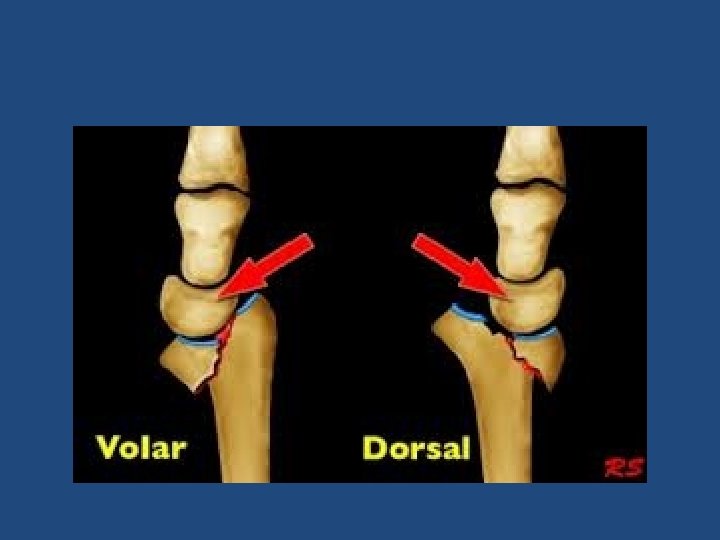

• Extra-articular: – Colles’ Fracture: dorsal angulation, shortening and radial deviation – Smith’s fracture: shortening and volar angulation. (reverse Colles’) • Intra-articular: – Barton’s fracture: volar or dorsal – others

Colles’

Smith’s